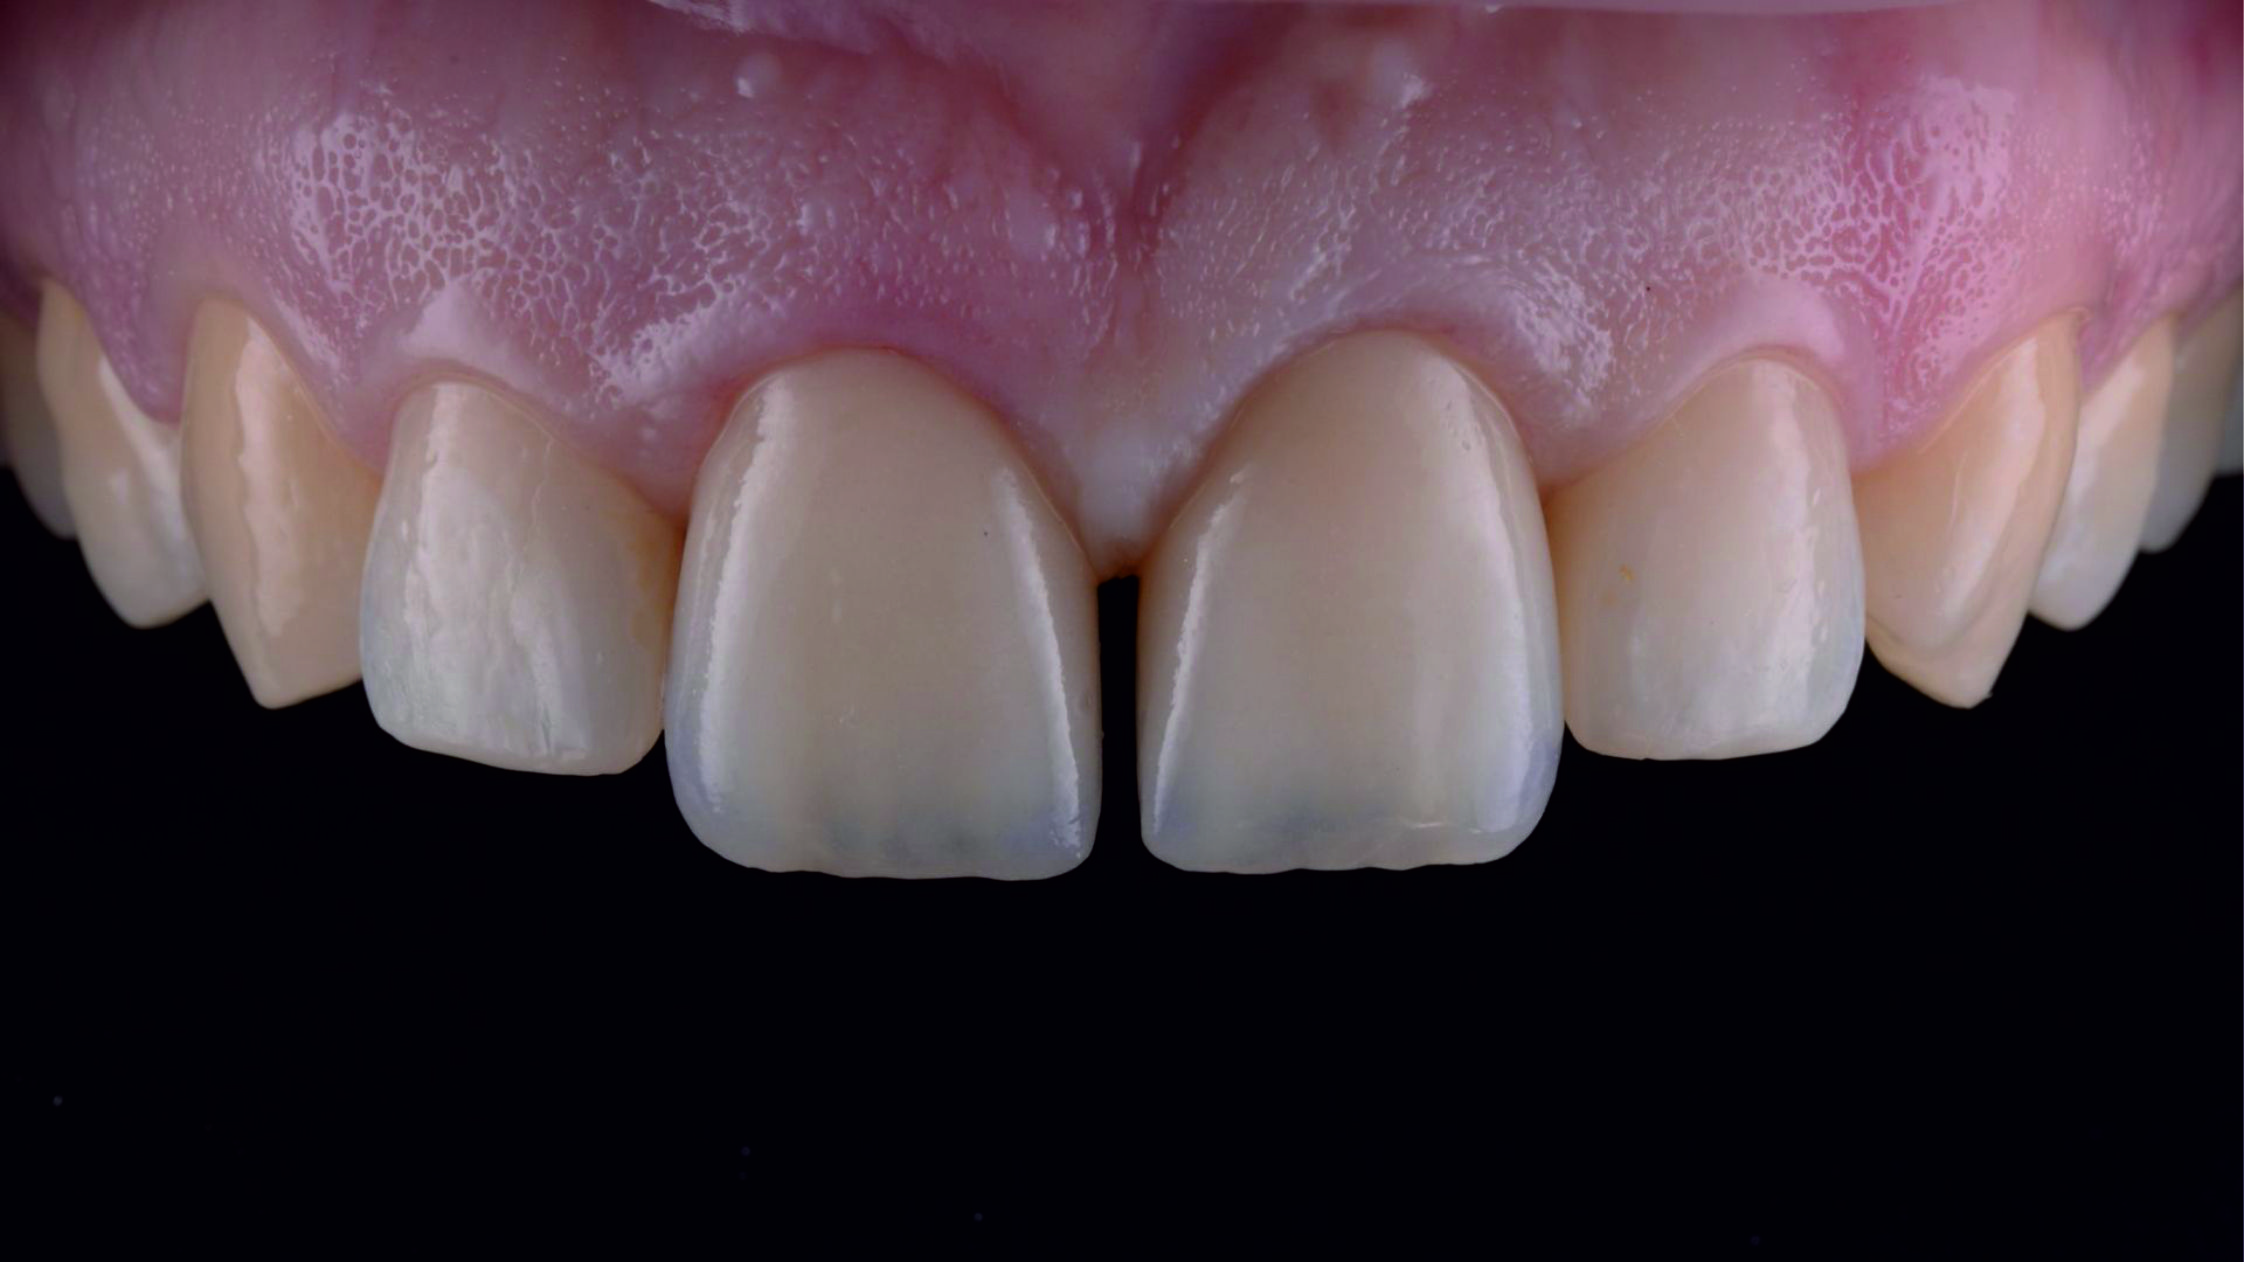

Фото 29. Виготовлені в лабораторії суцільнокерамічні реставрації з дисилікату літію.

Фото 30.

Фото 31. На етапі примірки ми перевірили реставрації щодо відповідності параметрів і форми, розрахованих нами за допомогою тимчасових конструкцій. Для цього ми встановили реставрації поруч одна з одною.

Фото 32. Примірка кінцевих реставрацій.